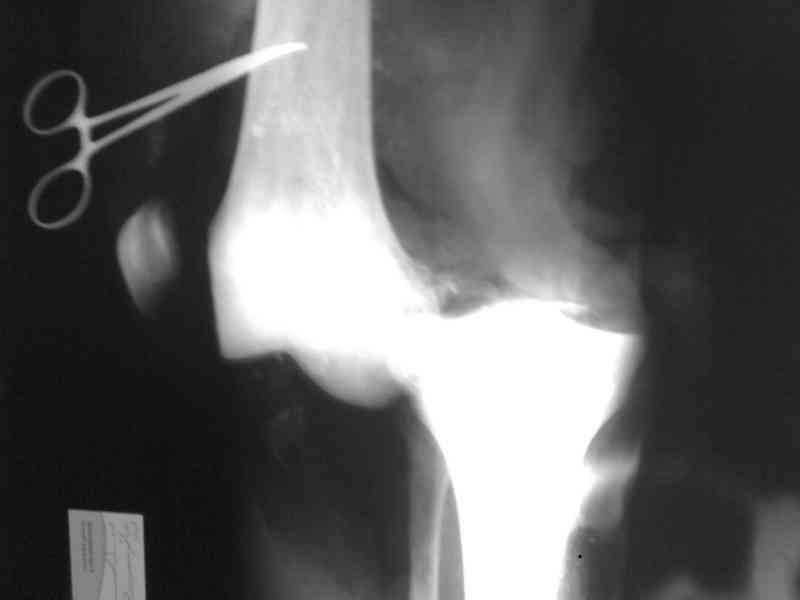

Bolnoi 27 let, DTP, Motorcycle trauma, postupil v kreane tiajelom sostoianii, osnovnia trauma- otkrity totalny vivih levogo kolennogo sustava s povrezdeniem malogo bersovogo nerva, tracionnoi povrezdenia podkolennoi arterii bez narushenia selostnost' sosuda, pomosh' okazanno v nujnum obmeme, kakoe ze mnenie uvazaemih kolleg naschet dalneshego vvedenia bolnogo? Castro

Uvajaemiy kollega! *Pomosh okazano v nujnom ob`eme*- kak ponyat? Vosstanovili krestoobraznih i bokovih svyazok? ili prosto vivih vpravili i fiksirovali AVF. sudya po R-snimkam nadkolennik nahoditsya visoko- znachit povrejdena i sobstvennaya svyazka, kotoraya ne ushita. Potom mojno sostavit plan lecheniya. S uvajeniem Abdurashid.

Доктор Castro,

На ренгенограмме хорошая аппозиция костей коленного сустава, но надколенник находится подозрительно высоко, поэтому необходимо убедиться в отсутствии повреждения связки надколенника.

Наличие пульсации на конечностях еще не доказательство отсутствия интимальных повреждении сосудов, наблюдались вторичные осложнениия, поэтому важна консультация сосудистого специалиста.

Снимки прошлых публикации из моего Power point